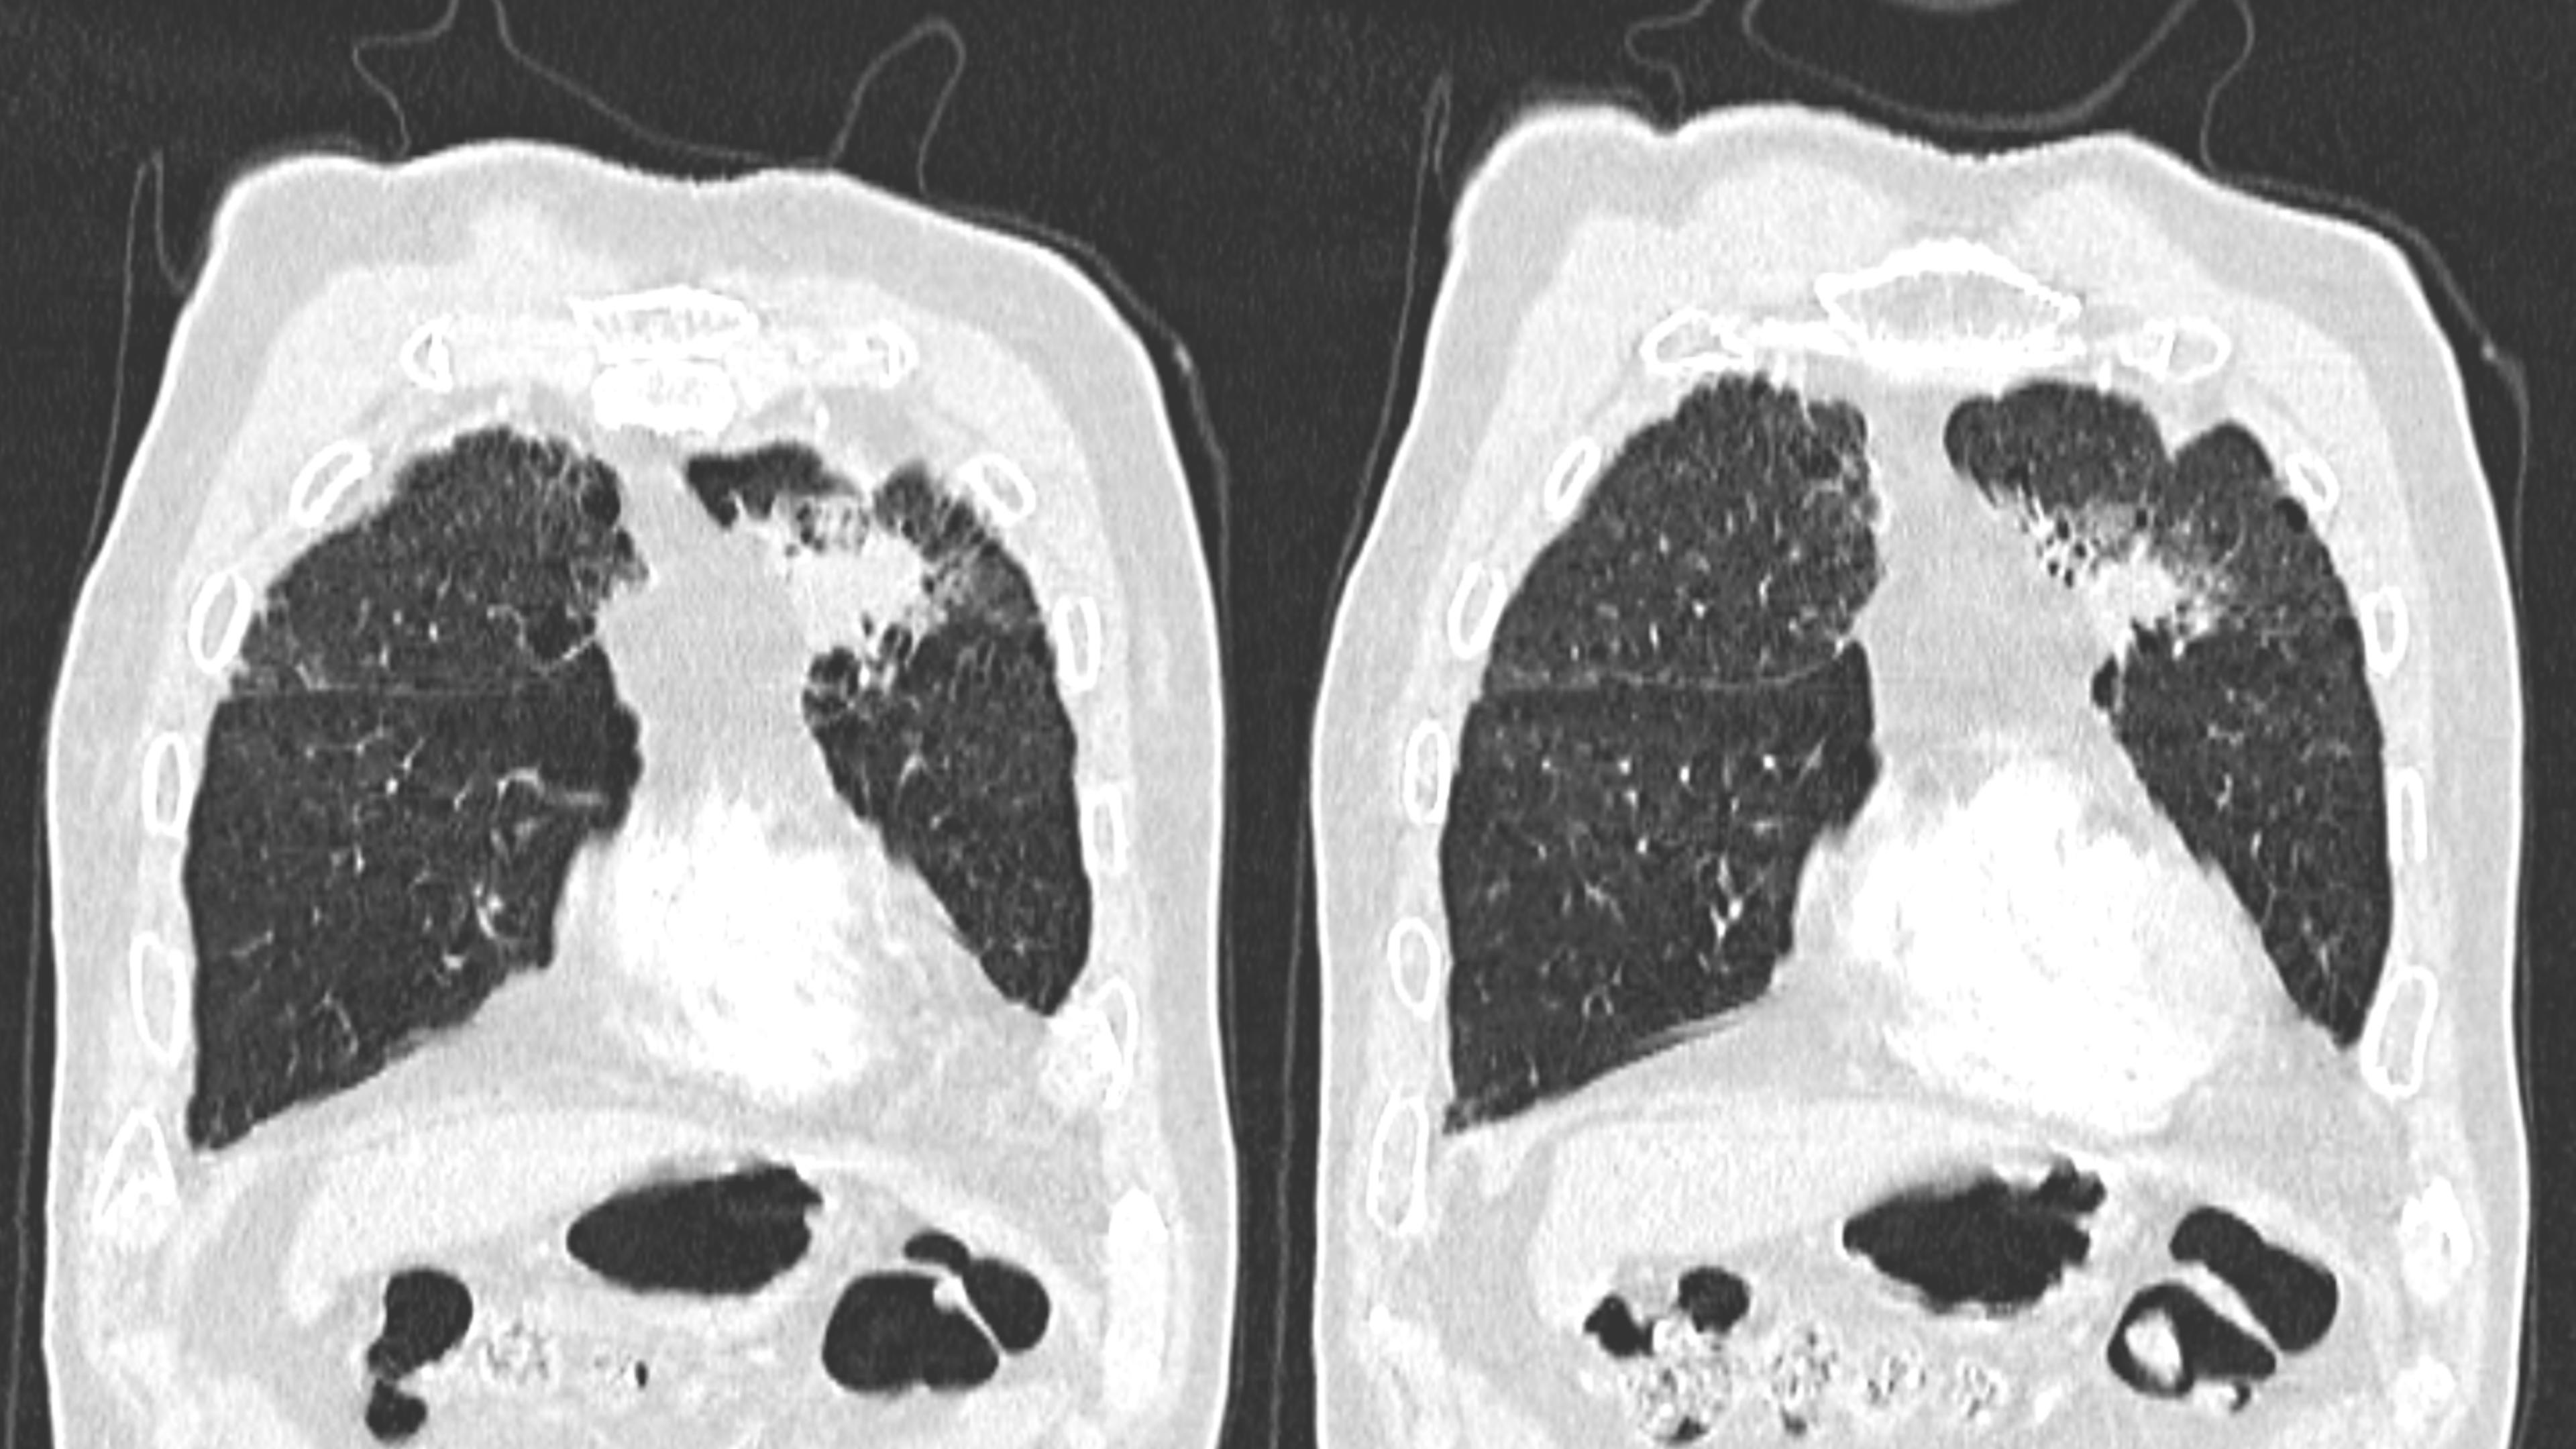

肺腺癌-鼎湖社群读片病例